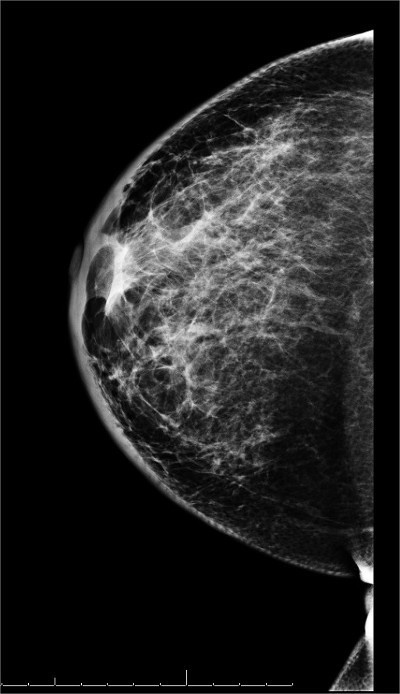

- Previously, there was no consensus on the optimal time intervals for imaging evaluation of patients following breast-conservation surgery:

- Many practices performed 6-month interval mammography of the treated breast for a variable number of years in an effort to monitor post-procedure changes

- The usefulness of short-term follow-up mammography in women undergoing breast conservation has been challenged:

- Retrospective studies have verified that the yield from a 6-month follow-up mammogram on the affected side is:

- Low (≤ 1%)

- Therefore, the ACR and ASCO recommendations are:

- To perform a bilateral mammogram at 12 months from the initial mammogram:

- Which should be at least 6 months following completion of radiotherapy:

- And should include a diagnostic mammogram on the affected side and a screening mammogram on the nontreated side

- Bilateral annual mammography is recommended thereafter

- Elimination of the 6-month and 18-month interval diagnostic mammograms after breast conservation:

- Should spare women unnecessary anxiety, discomfort, and inconvenience while lowering costs and improving efficiency